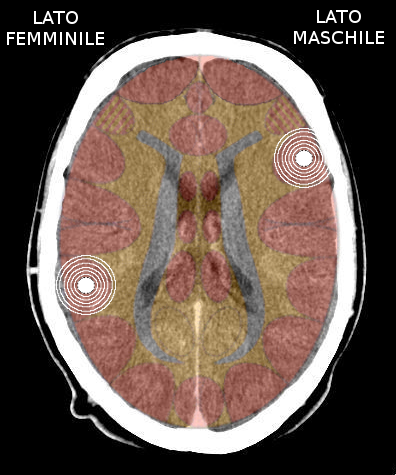

- Requisiti: Si è in costellazione schizofrenica quando due attivazioni colpiscono i due emisferi cerebrali di uno stesso livello:

- le due emiparti del tronco cerebrale;

- i due emisferi cerebellari;

- i due emisferi cerebrali (midollo e/o corteccia).

- NON È COSTELLAZIONE quando due attivazioni interessano due livelli cerebrali differenti, anche se occupano i due emisferi.